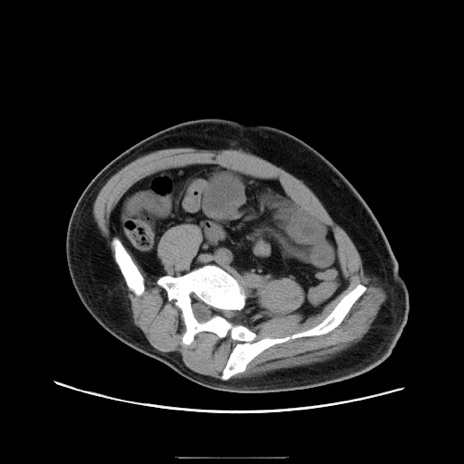

症例22(横断像)

【症例】50歳代男性

【主訴】腹痛

【現病歴】AVMからの被殻出血のため回復期リハ病棟入院中。 本日午後3時頃急に下腹部痛が出現した。

【既往歴】AVM、被殻出血、虫垂炎、高血圧

【身体所見】意識晴明、左半身不全麻痺、会話の理解は良好、36.5°C、腹部:膨隆、全体に板状硬、下腹部正中に圧痛点あり、反跳痛-、筋性防御不明、右下腹部にope scar

【データ】WBC 9400、CRP 0.06